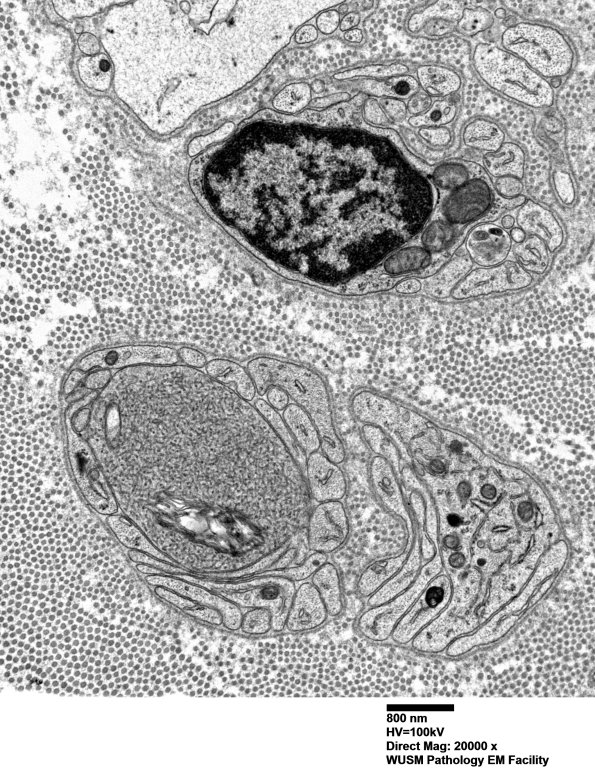

11OA1,2 A membranous cleft is surrounded by tubulovesicular elements. (electron micrographs)